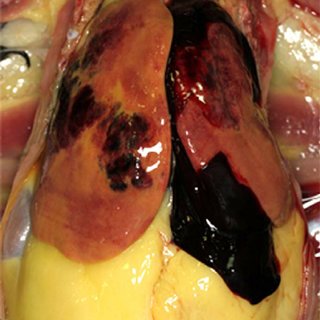

Fatty Liver Hemorrhagic Syndrome (FLHS) atau dikenal dengan perlemakan hati adalah kondisi berlebihnya lemak pada hati ayam. Asupan nutrisi secara berlebih (energi) dalam ransum dan tidak sesuai kebutuhan merupakan faktor penyebab utama perlemakan hati pada ayam. Selain itu disebabkan perbandingan protein yang tinggi, defisiensi kalsium, dan konsumsi pakan berlebih.

Fatty Liver Hemorrhagic Syndrome                                                                                                                          Perlemakan Hati

Apabila dilihat saat bedah bangkai, hati bengkak, berwarna pucat kekuningan dan terjadi pendarahan. Di dalam rongga perut akan ada akumulasi lemak dalam jumlah besar. Selain karena asupan nutrisi secara berlebih, FLHS dapat disebabkan karena variasi strain unggas dan stres secara akut juga akan meningkatkan pembentukan lemak (lipogenesis).